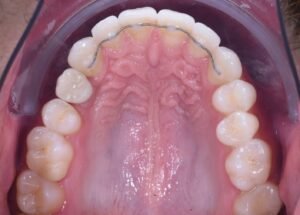

Stap 3: tandvleescorrectie

Voor een natuurlijk en duurzaam esthetisch resultaat versterkten we het tandvlees rond het implantaat. Hiervoor verplaatsten we een klein stukje tandvlees uit een andere mondzone en hechtten dat op de implantaatlocatie. Dit ondersteunt zowel gezondheid als een natuurlijke uitstraling van het tandvlees rondom de nieuwe tand.

Stap 5: plaatsing van de definitieve kroon

Als het implantaat volledig is ingebouwd en stabiel, wordt de definitieve kroon vervaardigd en geplaatst. Deze kroon wordt op maat gemaakt: kleur en vorm stemmen we af op uw natuurlijke gebit. Het eindresultaat is een tand die qua uitstraling en functie nauwelijks van uw eigen tanden te onderscheiden is.